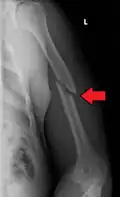

A transverse fracture of the humerus shaft -

Middle fractures are usually caused by either physical trauma or falls. Physical trauma to the humerus shaft tends to produce transverse fractures whereas falls tend to produce spiral fractures. Metastatic breast cancer may also cause fractures in the humerus shaft.[12] Long spiral fractures of the shaft that are present in children may indicate physical abuse.[5]